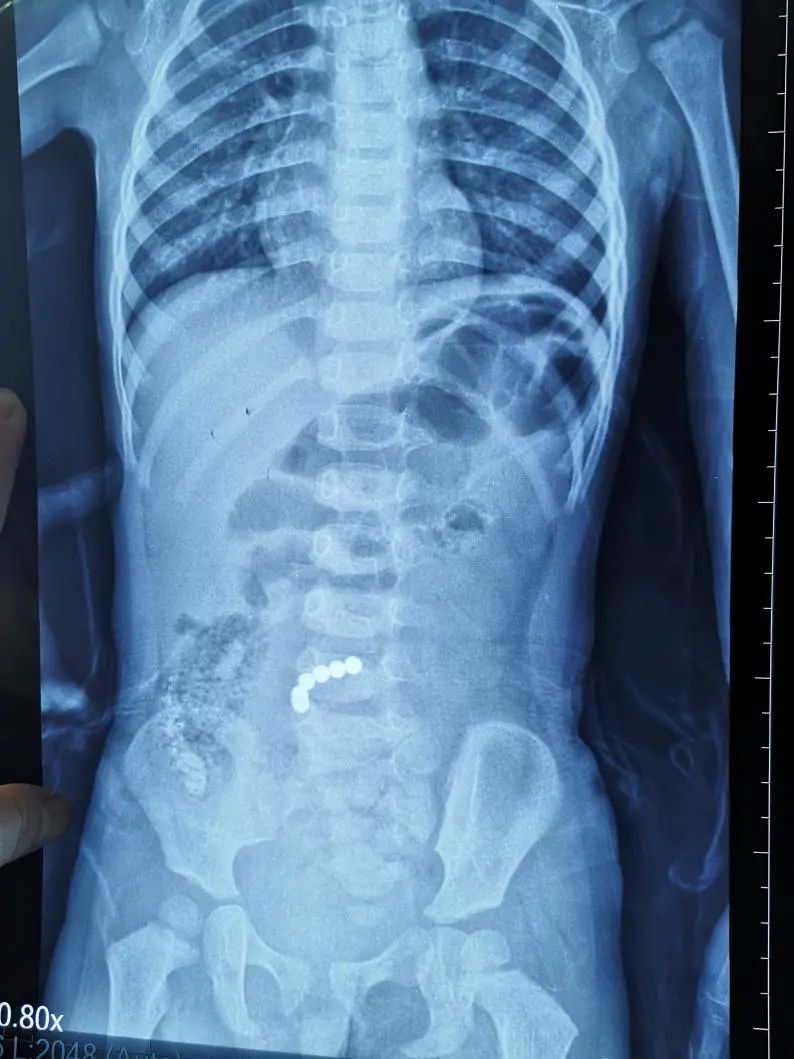

隨著孩子腹痛加重,父母立馬帶著她來(lái)到中山大學(xué)附屬第六醫(yī)院,入住兒科,經(jīng)腹部平片、CT等相關(guān)檢查,確診為小腸異物,明確磁力珠位于空腸上段,兒科馬上聯(lián)系消化內(nèi)鏡科,擬經(jīng)小腸鏡取出磁力珠。

女童腹部平片圖片

經(jīng)過(guò)術(shù)前準(zhǔn)備,消化內(nèi)鏡科郭勤副教授進(jìn)行小腸鏡檢查,發(fā)現(xiàn)距淼淼屈氏韌帶約30cm處空腸梗阻,小腸鏡無(wú)法通過(guò),遂聯(lián)系小兒外科王德娟主任醫(yī)師考慮手術(shù)取異位。王德娟團(tuán)隊(duì)在淼淼臍部打一個(gè)小洞放入腹腔鏡,探查發(fā)現(xiàn)磁力珠已經(jīng)穿出空腸,并造成多處腸管、腸系膜穿孔,立即改行開(kāi)放手術(shù)剖腹探查。